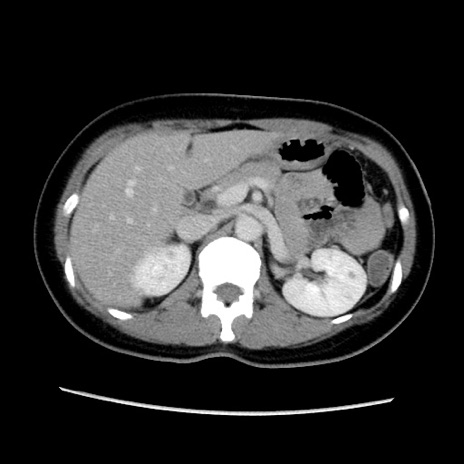

症例39(横断像)

【症例】40歳代女性

【主訴】上下腹部痛

【現病歴】2日目から下腹部痛あり。夜間は痛みで眠れなかった。昨日より上腹部痛と下痢が出現。臥位で痛みは軽快したため、休んでいた。本日になって臥位でも立位でも痛みが強くなってきたため救急要請。

【既往歴】子宮内膜症

【身体所見】部:平坦・軟、左上下腹部に圧痛あり、反跳痛あり。

【データ】WBC 21800、CRP 26.78